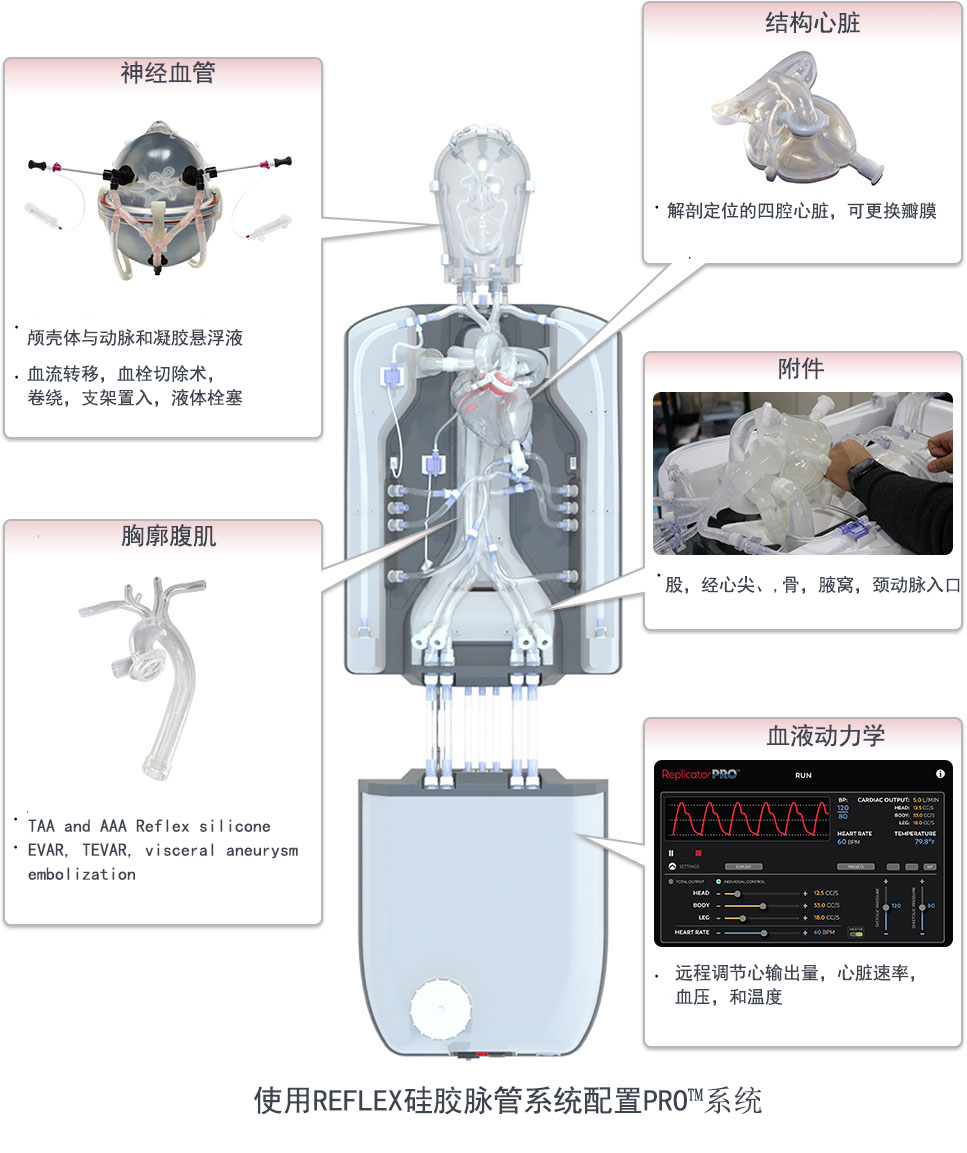

一、PRO的血管内复制系统——体验逼真的心脏驱动的逼真的生理复制

通过人血流动力学特征和逼真的触觉反馈,通过用户友好,强大且可重复的模拟来增强培训和发展。?wu限能力

复制各种血管内手术和疾病状态。

可重复且坚固

重复模拟具有真正生理功能的血管内病例。?生理和解剖学上准确的人类硅胶血管?在模拟血管内手术时,PRO?可提供的逼真的模拟体验:

●标准血管,神经血管和瓣膜疾病状态

●可应要求提供针对患者的定制血管

●用户控制的血流动力学,具有快速起搏能力

●具有清晰视野的多种成像模式– CT,荧光检查和照相机

●执行EVAR,TEVAR,FEVAR,TAVR等

二、 神经血管流系统

神经血管

急性缺血性中风

动脉瘤

动静脉畸形

三、的神经血管复制系统

复制器

的血管内复制系统

复制器的血液动力学te性可提供类似于生理流的真实心输出量,从而为设备开发和培训提供了真正的设备性能。

wu限的神经血管配置

为头或盒配置易于更换的多种神经血管疾病状态。

具有重复性的类似生活的结果

在产品演示,培训课程等中轻松且反复地模拟过程。